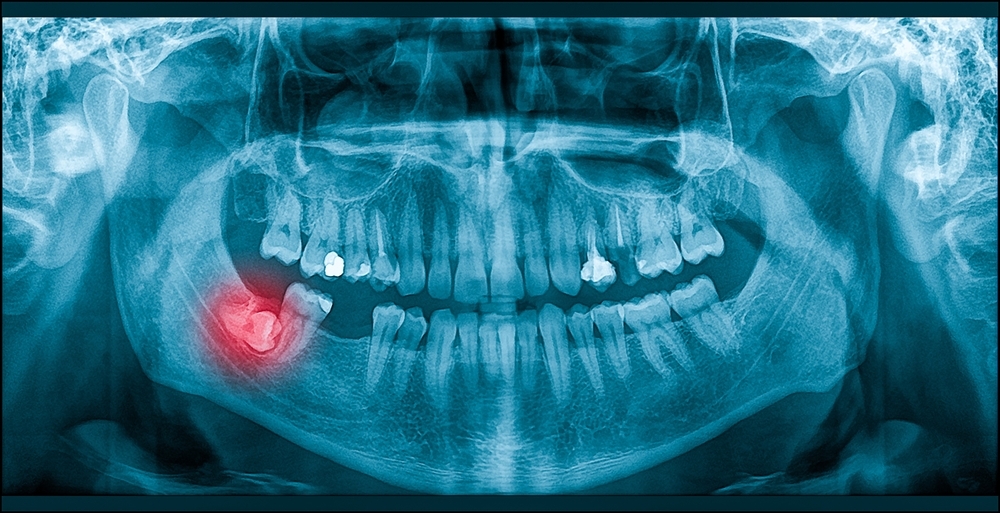

Tandklinikken Kongensgade tilbyder nye patienter en grundig tandundersøgelse (DG) samt 2 røntgenbilleder (Bitewings) hvis der er behov for dette. Alt sammen til en fair pris på kun 428,73 kr. Vi undersøger tænderne grundigt for alle synlige skader dvs. plak, begyndende caries, slimhindelidelser og eventuelle parodontose.

Desuden tager vi røntgenbilleder (Bitewings) af tænderne, for at vi kan opdage eventuelle skjulte problemer.